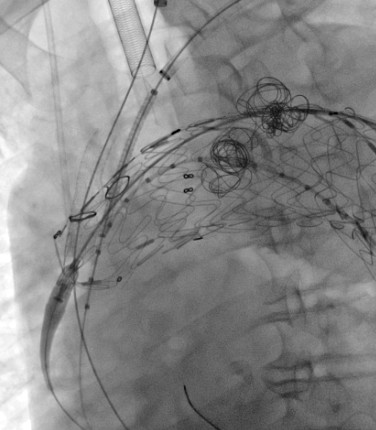

穿刺股动脉、切开颈动脉、肱动脉建立入路,超选内漏口、栓塞瘤腔,体外预开窗、重建弓上动脉......血管外科两组人马同时开工,有条不紊。在麻醉科林芩主任团队的密切配合下,一系列步骤紧张有序地进行着。手术持续了4个多小时,当最终的造影确认内漏完全封闭、假性动脉瘤成功隔绝,并且主动脉弓上的重要分支动脉血供良好的那一刻,血管外科团队成员都已忘却了身上几十斤的铅衣和满身的汗水。夏印主任和黎成金主任不禁对视一笑:“拆雷成功,又救了一条命。”

弹簧圈栓塞瘤腔